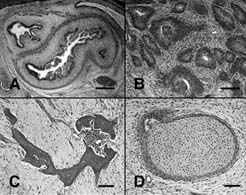

cellssm2.JPG

9.88

cell